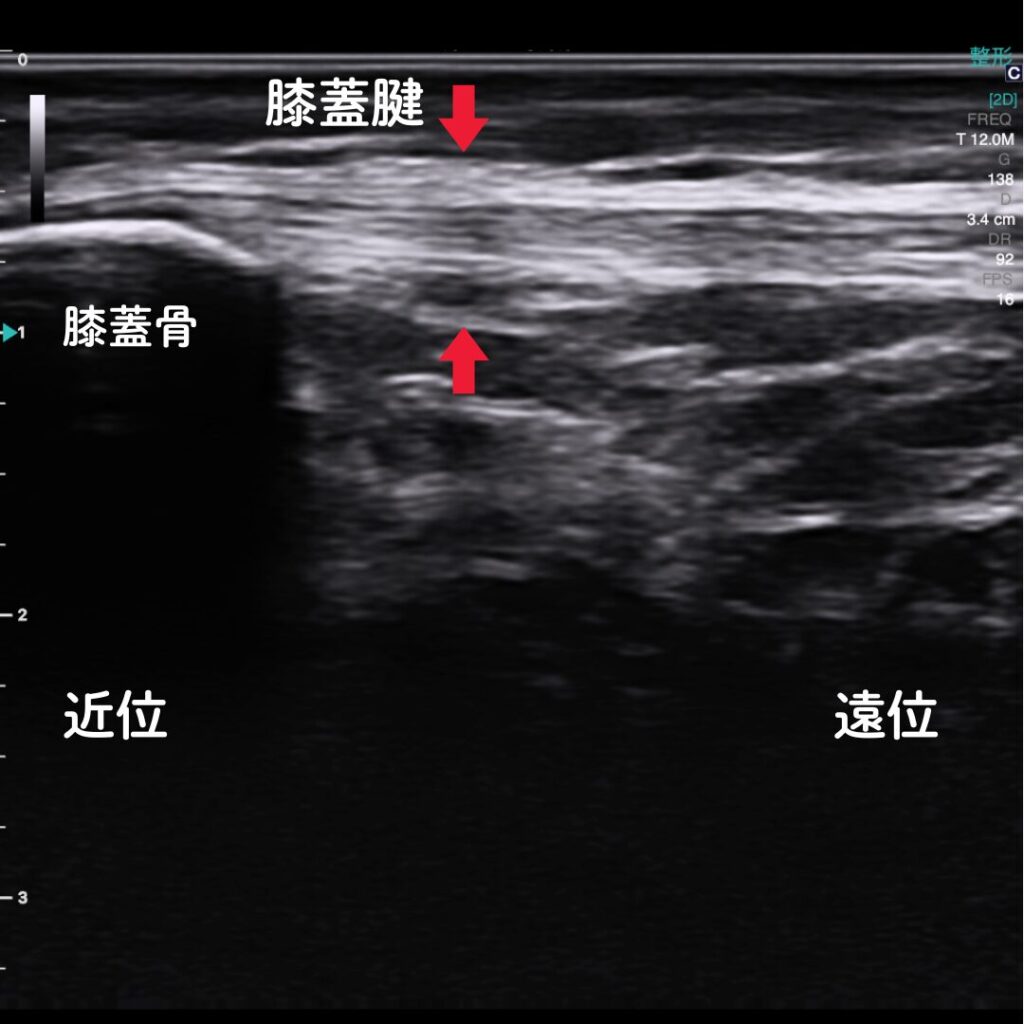

🔶エコー(超音波観察装置)で原因を“見える化”

エコー観察により、膝蓋腱の炎症や損傷の程度をリアルタイムで確認できます。

レントゲンでは写らない腱や軟部組織の状態を可視化し、痛みの原因を正確に特定します。

また腱付着部の骨異常も観察可能。